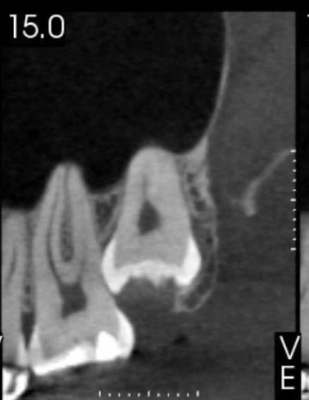

Veja alguns casos de sucesso